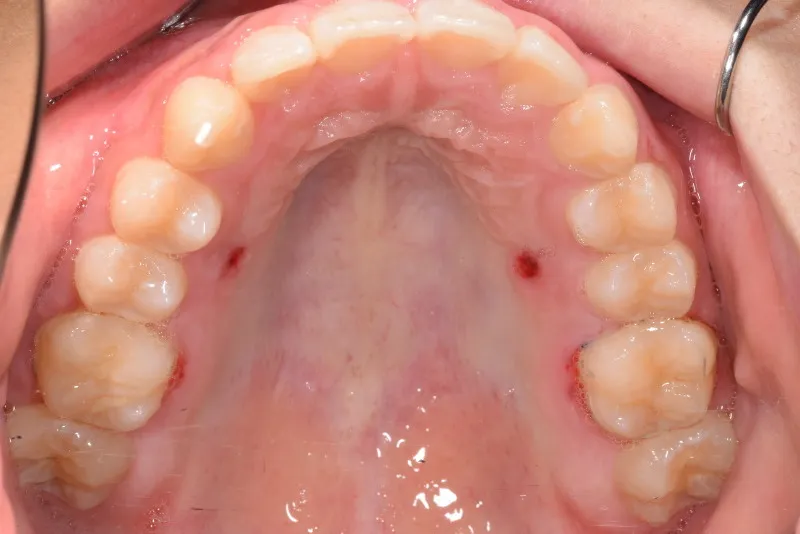

上下の幅が狭くガタガタに生えています。

乳歯があるうちはオリジナル矯正装置を使用しました。

初診